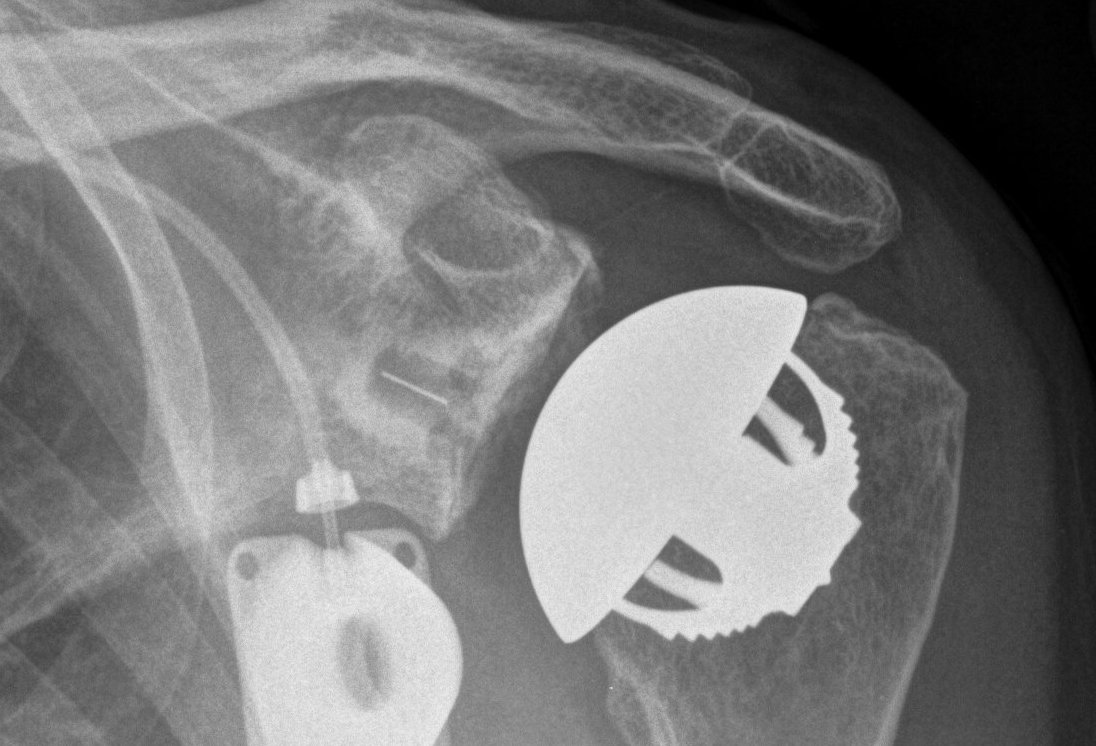

Glenoid component

Glenoid center point crucial

Vault is a triangle

- pilot hole critical

- must not penetrate vault with keel or peg drilling

- get vault perforation / blowout

- cannot pressurise cement

Vault blowout / perforation

1. Freehand technique

- identify center of glenoid articular surface

- glenoid center point slightly inferior and anterior to center of the articular surface glenoid

- match inclination of glenoid

- insert guide pin aiming anteriorly

2. 3D CT templating

- templates glenoid component

- creates guide that matches glenoid

- allows placement of guide pin

Insert guide pin

- ream only articular cartilage

- preserve subchondral bone

- reamers often semi-circle to aide insertion and removal

Ream peg / keel

- ensure no blowout with arthroscopy probe

Glenoid cementing

- keep holes dry

- insert cement into peg / keel holes using syringe

- no cement under poly as is generally too thin and will crack

- pressurise

- insert poly